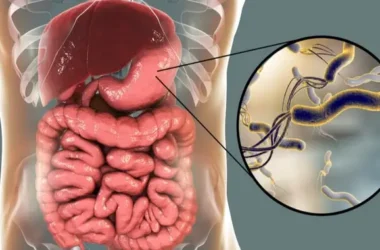

تآكل اللثة، المعروف أيضاً بانحسار اللثة، هو حالة تحدث عندما تتراجع أنسجة اللثة التي تحيط بالأسنان وتنكشف جذور الأسنان. في الوضع الطبيعي، تغطي اللثة جذور الأسنان وتحميها.

عندما تتآكل اللثة، تتكون فراغات أو “جيوب” بين الأسنان واللثة. هذه الجيوب تُصبح بيئة مثالية لتكاثر البكتيريا الضارة، مما قد يؤدي إلى مزيد من الضرر للأسنان وهيكل العظم الداعم لها.

يُعد التهاب اللثة المزمن أحد الأسباب الرئيسية لتآكل اللثة. البكتيريا الموجودة في البلاك تتسبب في التهاب أنسجة اللثة وتدميرها تدريجياً، مما يؤدي إلى انحسارها.